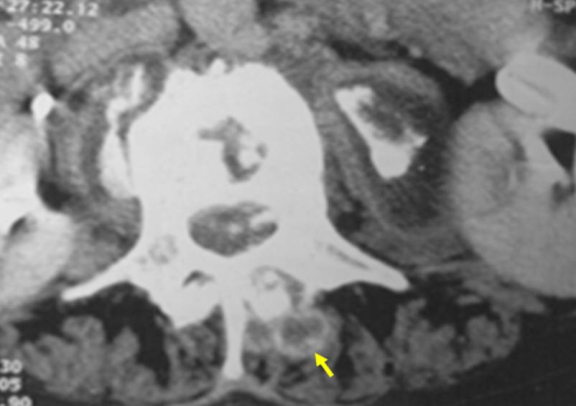

布鲁氏菌脊柱炎 CT显示椎间盘、椎体和小关节受累伴椎旁钙化(黄箭头)和硬膜外脓肿。